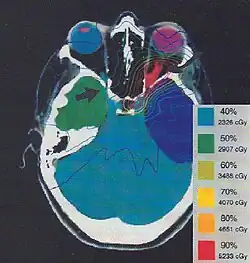

The more formal optimization process is typically referred to as forward planning and inverse planning.[12][13] Plans are often assessed with the aid of dose-volume histograms, allowing the clinician to evaluate the uniformity of the dose to the diseased tissue (tumor) and sparing of healthy structures.